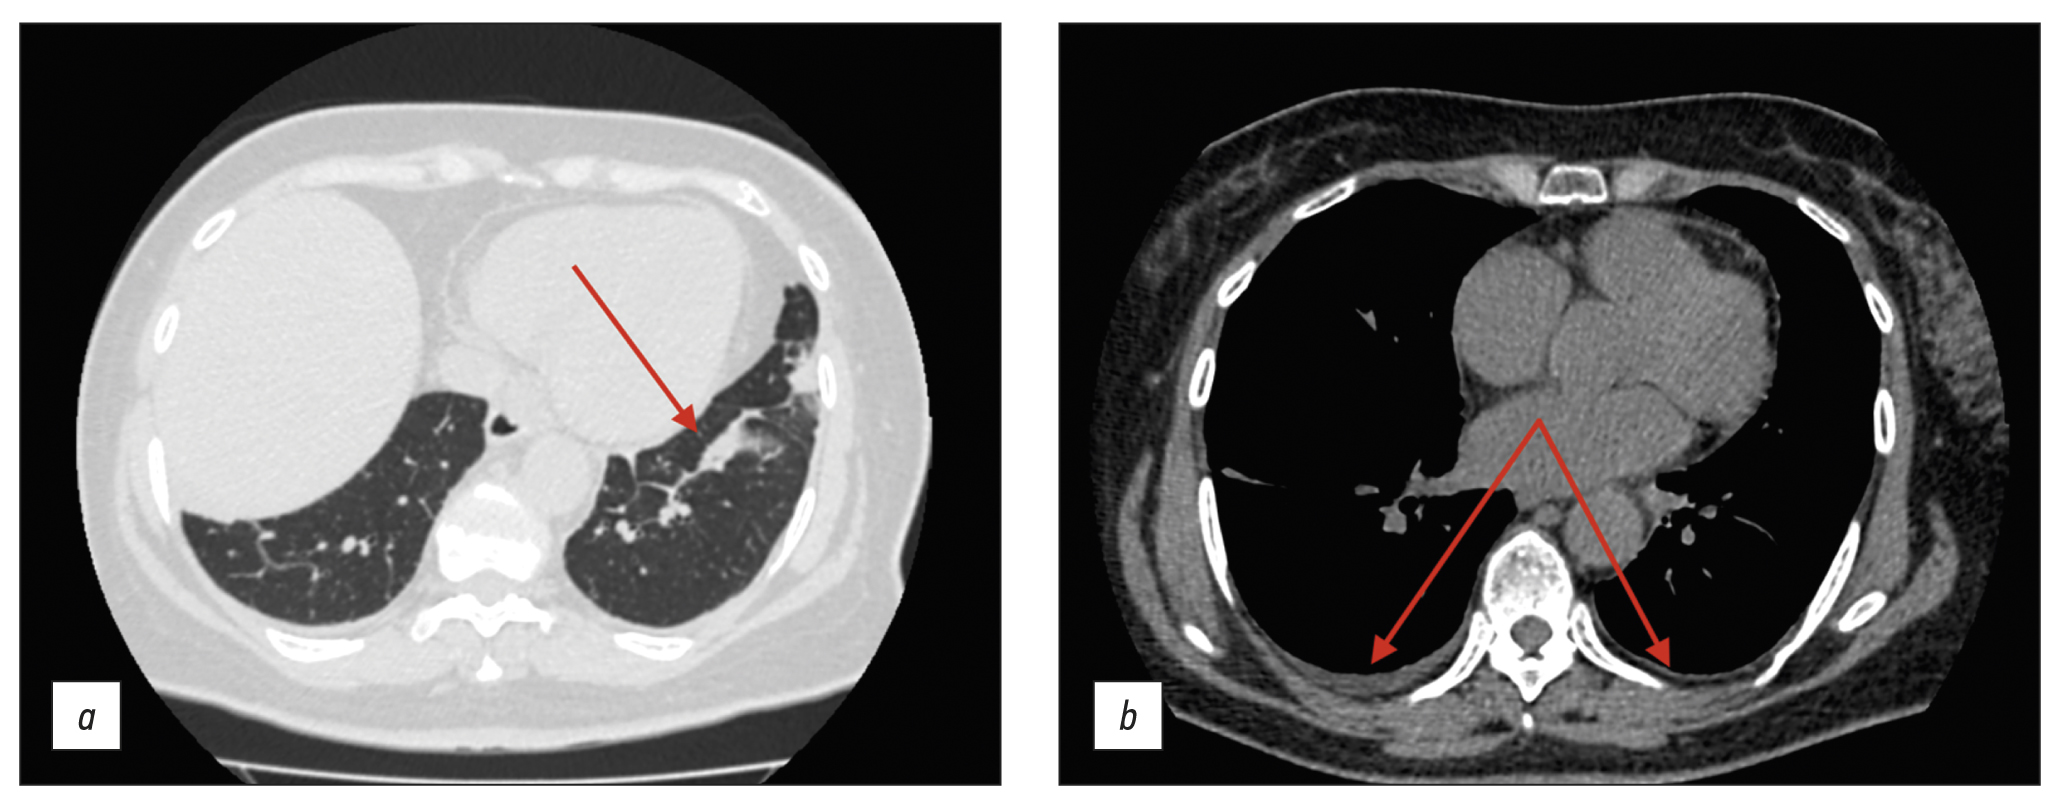

The findings were classified as lymphadenopathy, and the patient was referred to a hematologist in September 2020. A bone marrow trephine sample was conducted, followed by histological examination; no indication of the hematopoietic system was identified. Compared with the earlier scan in August 2020 (see Figure 1), follow-up thoracic CT (Figure 3) revealed effusion resorption from the pleural cavities and partial regress of hypoventilatory changes in the basal parts of the lungs. Otherwise, no significant changes were found.

Fig. 3. Thoracic computed tomography scans (September 2020); axial plane: the red arrows show (a) the area with partial regression of the hypoventilation changes and (b) lack of pleural effusion.